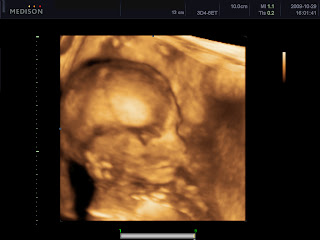

Kép